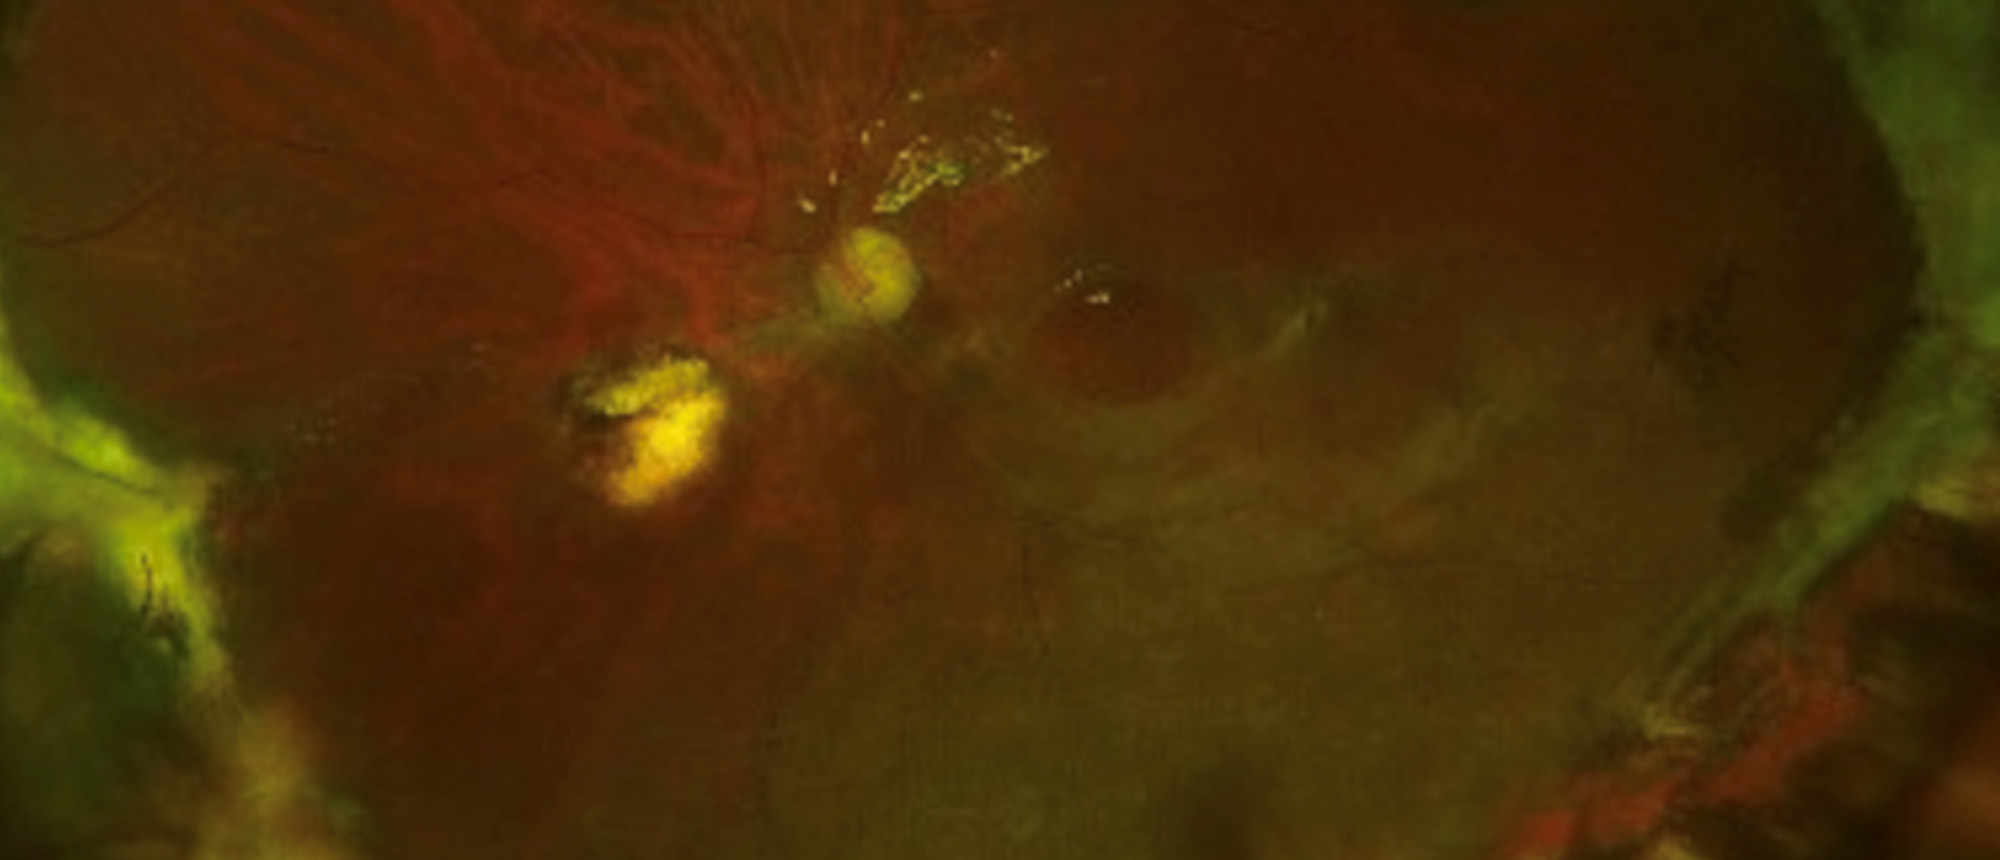

A patient with history of recurrent rhegmatogenous retinal detachment and refractory macular hole presented to the Bascom Palmer emergency room with elevated left eye pressure. Examination showed silicone oil bubbles in the angle, recurrent inferior retinal detachment and a recurrent large full thickness macular hole. Surgical management with pars plana vitrectomy, silicone oil exchange, retinectomy, and amniotic membrane graft placement was performed. Post-operatively, the retina was attached, ocular pressure was normal, macular hole was closed, and vision was stable.